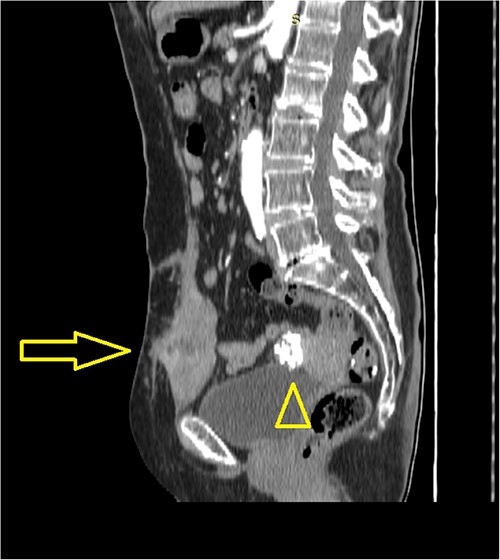

A 73-year-old female patient was admitted to our hospital due to the existence of a tumor in the abdominal wall proved to be a metachronous adenocarcinoma metastasis. In October 2015, the patient was treated for rectosigmoid adenocarcinoma when rectosigmoid resection with primary anastomosis was performed. Pathology report revealed tumor stage I (pT2, pN0, pM0, pL0, pV0, pR0, G2, NG2). Only three lymph nodes were harvested and reported to be negative by the pathologist. Nevertheless, the oncologist decided not to initiate adjuvant chemotherapy, and recommendations for routine outpatient check-ups were advised. Two postoperative routine colonoscopies with normal findings were performed (in 2016 and 2022). Shortly after the second colonoscopy (in September 2022), elevated values of serum tumor markers were detected: Carcinoembryonic antigen (CEA) value of 15.2 ng/mL and Carbohydrate antigen (Ca) 19–9 value of 47.3 U/mL. The oncologist initiated adjuvant treatment with eight cycles of oxaliplatin and capecitabine. In March 2023, the additional elevation of markers followed (CEA value of 58.64 ng/mL, Ca 19-9 value of 665.12 U/mL, and Cancer antigen 15-3 value of 32.5 U/mL). In June 2023, serum marker levels decreased (CEA value of 35.5 ng/mL and Ca 19-9 value of 147 U/mL). Physical examination on routine follow-up revealed a palpable painless mass in the midline suprapubic region without skin involvement. Abdominal computerized tomography presented a solid tumor mass in the abdominal wall with dimensions of 70 × 40 × 80 mm and it was described as a suspected metastatic deposit by the radiologist (Figs 1 and 2). Core biopsy under ultrasonography guidance confirmed the presence of metastatic adenocarcinoma ˃7 years after the primary colon cancer surgery. A decision upon surgical removal was brought. The lesion was excised (Figs 3 and 4) and the defect of the abdominal wall was reconstructed by the use of composite mesh (Fig. 5). The postoperative course was uneventful and the duration of stay was 7 days. The pathology report confirmed the presence of metachronous metastasis from colon adenocarcinoma. Metastasis was measured to be 10 × 6 × 5 cm, completely occupied by a neoplastic infiltrate (Fig. 6). Immunohistochemistry staining showed positivity on Caudal-type homeobox 2 (CDX2) and Cytokeratin 20 (CK20) thus proving the origin of the metastatic deposit from colorectal adenocarcinoma (Fig. 7A–C).

Abdominal computerized tomography (sagittal scan) shows a tumor in the abdominal wall (arrow) with the secondary finding of calcified uterine myoma (arrowhead).